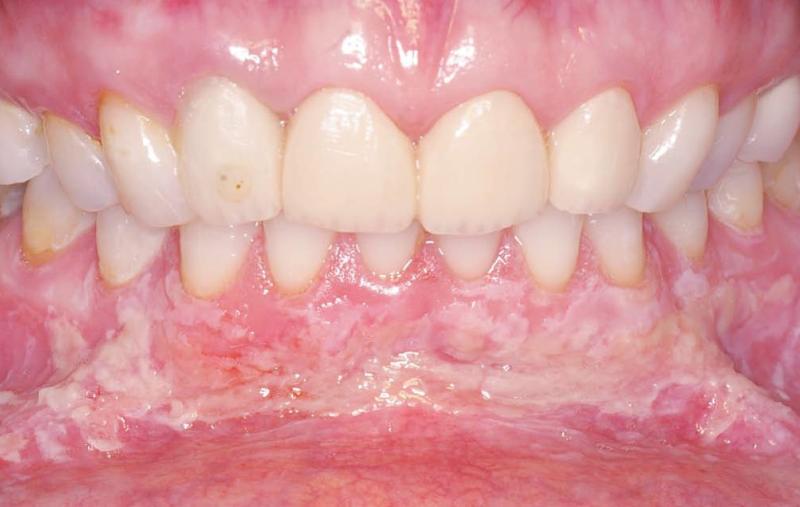

CASO CLÍNICO LXIII

Diagnóstico anatomopatológico e inmunopatológico